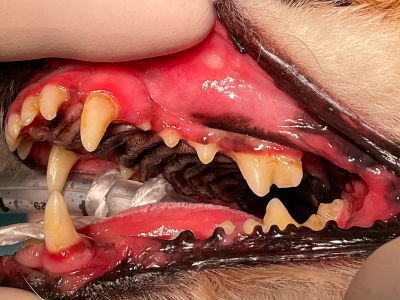

投薬治療中

内科治療中(ステロイドは使用していません)。頬粘膜に柔軟性が戻りました。

歯垢をためないよう、歯みがき教室にてブラッシング練習も続けています。 -